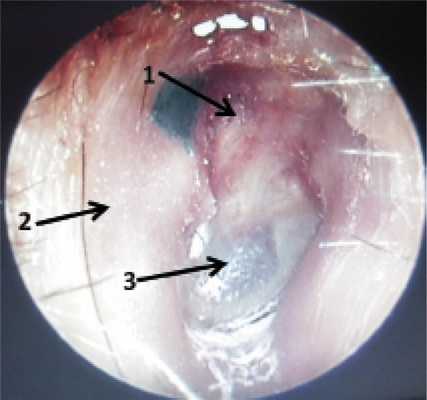

Через год после операции у 22 (88%) больных фиксировали хорошие результаты (рис. 1). Удовлетворительные результаты были достигнуты у 1 (4%) больного, что было обусловлено сохраняющейся реперфорацией неотимпанальной мембраны. Больному была выполнена реоперация с закрытием дефекта в неотимпанальной мембране. В 2 (8%) случаях потребовалась санирующая реоперация из-за рецидива отореи. Рецидив был обусловлен резидуальной холестеатомой, оставленной в тимпанальном синусе.

Рис. 1. Правое ухо. Отоэндоскопия отоскопом прямого видения 00 фирмы KARL STORZ. 1 — облитерированный эпитимпанум, 2 — задняя стенка наружного слухового прохода после полной мастоидопластики, 3 — неотимпанальный лоскут.